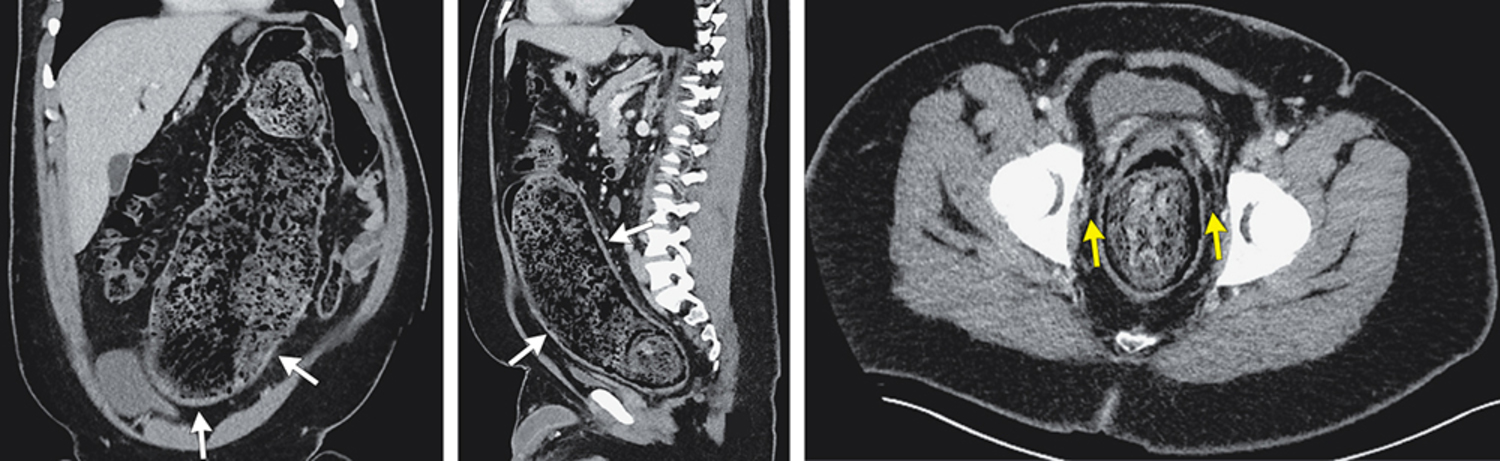

A 23-year-old man with autism spectrum disorder and chronic constipation presented to the emergency department with a 1-week history of abdominal pain on his left side, nausea, and vomiting. Physical examination was notable for abdominal distention and mild tenderness to palpation on the left side of the abdomen. Computed tomography of the abdomen and pelvis is shown. What is the most likely diagnosis?

CT 扫描显示结肠因大量粪便积聚而扩张,伴有肠壁增厚以及直肠周围脂肪组织条纹状模糊(perirectal fat stranding)。最终诊断为粪石性结肠炎(Stercoral colitis)。

在粪石性结肠炎中,长期滞留的硬便导致结肠扩张,从而引发炎症反应。在某些情况下,粪块(fecaloma)可能造成局部压力性坏死甚至穿孔。治疗包括积极调整肠道功能(如使用缓泻剂等),在部分病例中,还可能需要手动清除粪块(fecal disimpaction)。